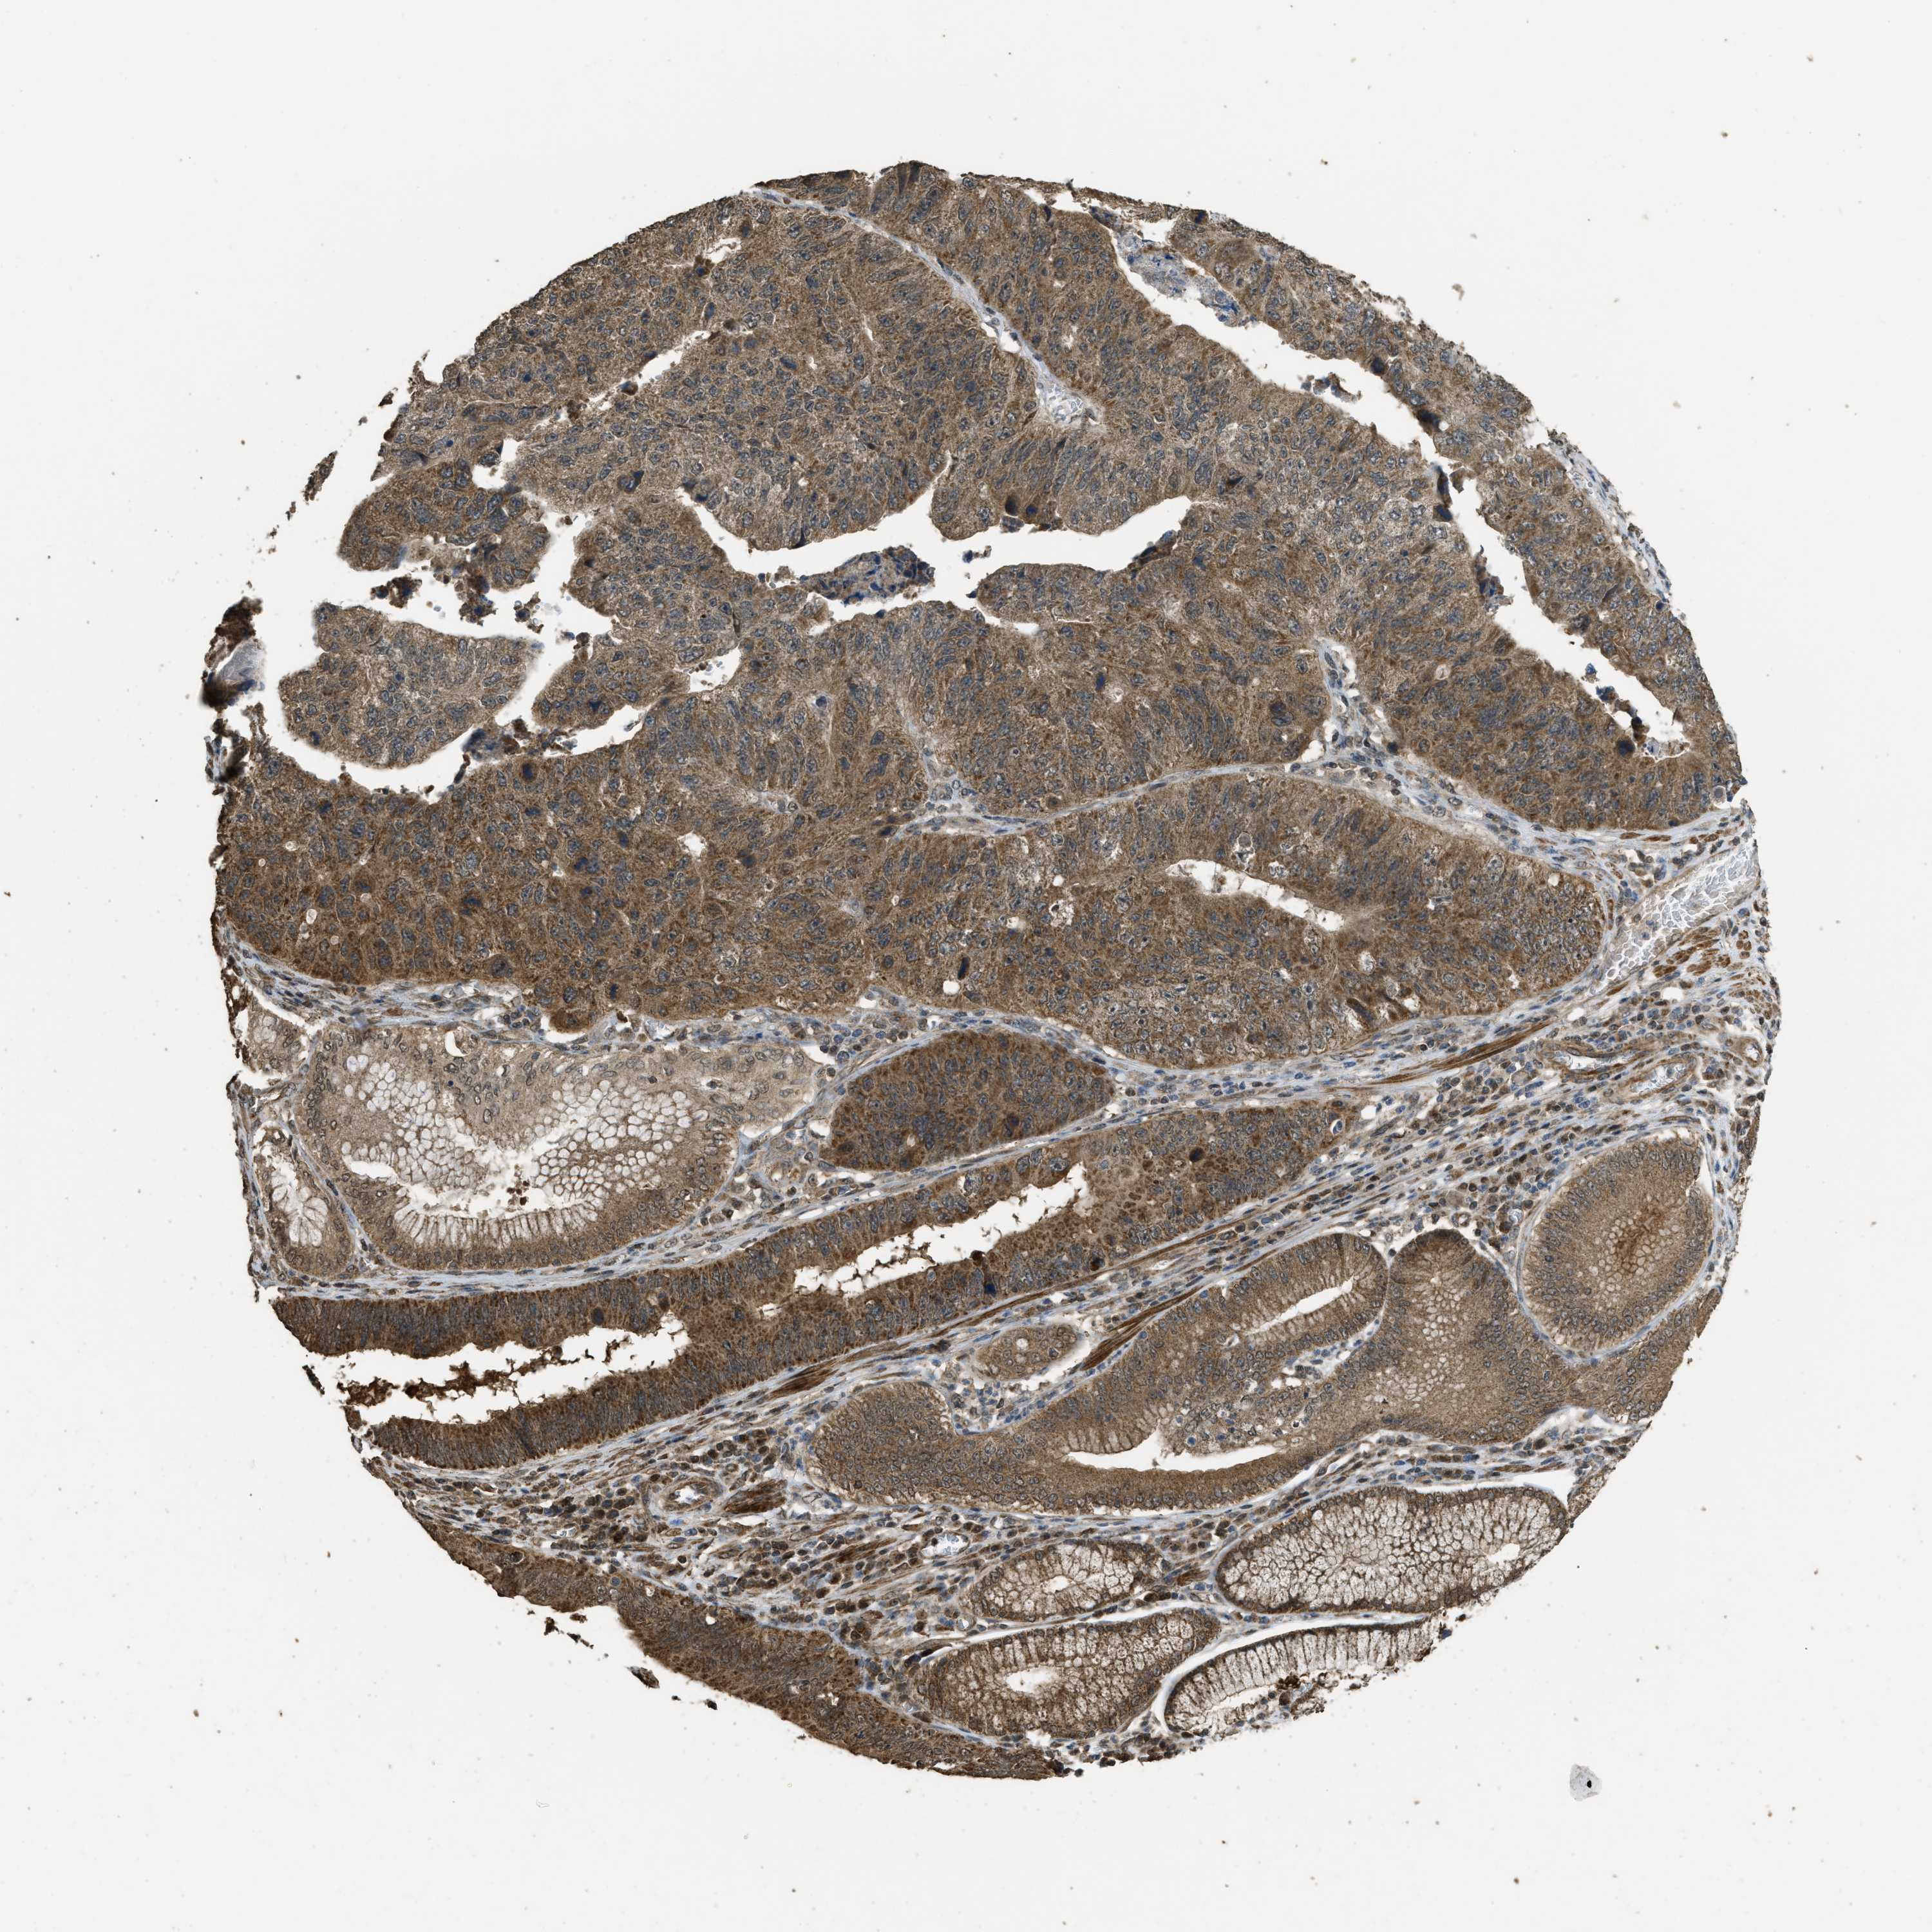

STOMACH CANCER - Protein expressioni

A mouse-over function shows sample information and annotation data. Click on an image to view it in a full screen mode. Samples can be filtered based on level of antibody staining by selecting one or several of the following categories: high, medium, low and not detected. The assay and annotation is described here.

Note that samples used for immunohistochemistry by the Human Protein Atlas do not correspond to samples in the TCGA dataset.

Antibody stainingi

Antibody staining in the annotated cell types in the current human tissue is reported as not detected, low, medium, or high, based on conventional immunohistochemistry profiling in selected tissues. This score is based on the combination of the staining intensity and fraction of stained cells.

Each image is clickable and will lead to virtual microscopy that enables deeper exploration of all samples and also displays staining intensity scores, fraction scores and subcellular localization as well as patient and tissue information for each sample.

Antibody HPA051322

Antibody CAB017111

Staining

High

Medium

Low

Not detected

Intensity

Strong

Moderate

Weak

Negative

Quantity

>75%

75%-25%

<25%

None

Location

Nuclear

Cytoplasmic/membranous

Cytoplasmic/membranous,nuclear

Adenocarcinoma, NOS

Adenocarcinoma, High grade